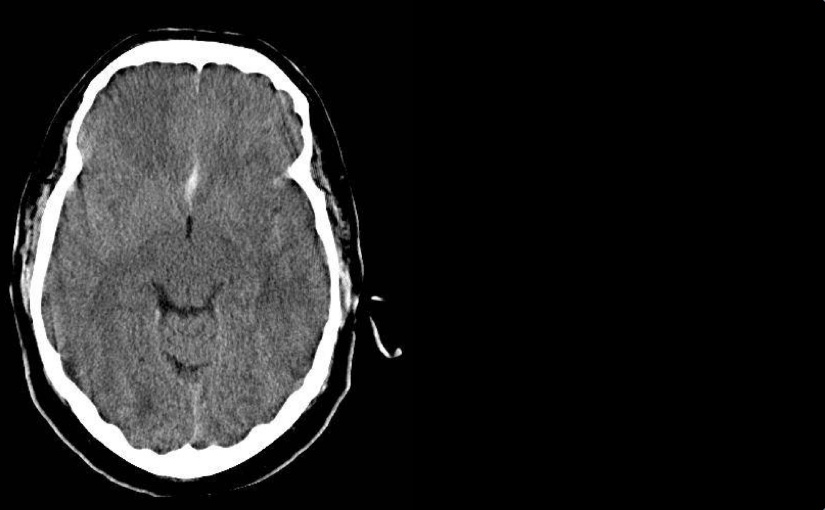

Vorwort Ja, wir sind keine Radiologen. Ja, in der heutigen Zeit, in der es immer mehr um medikolegale Konsequenzen unseres Tuns geht, sollten wir uns nicht überschätzen und selbst radiologische Befunde erheben ohne die formale Qualifikation dafür zu haben. Ja, auch fachärztliche radiologische Befunde sind oft falsch (oder mindestens diskutabel). Ja, ich erwarte von allen…